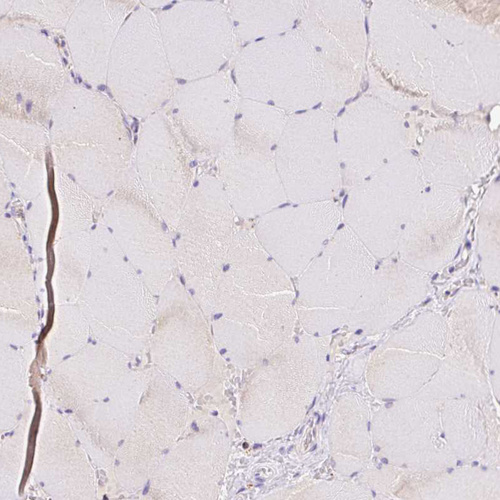

Immunohistochemistry analysis in human liver and skeletal muscle tissues using HPA051162 antibody. Corresponding PCK2 RNA-seq data are presented for the same tissues.